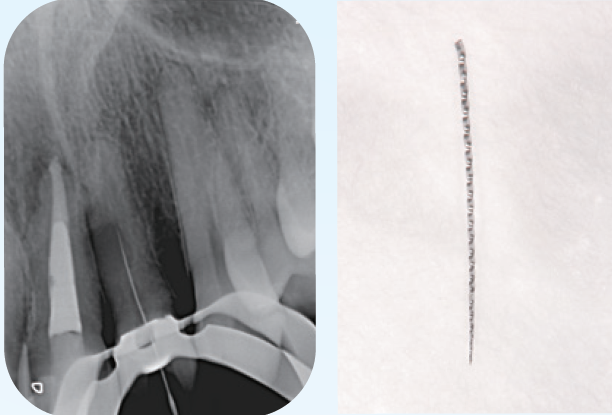

臨床症例3 その2

左上2番の感染根管処置

根中間部は狭窄しており根尖までは穿通障害歯である根中間部で異物を触知したため除去を行なった右は 、除去した破折ファイルを示す

臨床症例3 その3

①根管内の異物除去後のレントゲン像

②根中間部は狭窄しているものの細い号数のテーパーの少ないファイルで根尖までファイルを到達せせることができたのでEMRを測定しレントゲンを撮影した

③根尖は吸収度は少なく根尖孔径は#30で形成しガッタパーチャとMTAシーラーを用いて根管充填した

④根管充填後3ヶ月のレントゲン像

根尖周囲に見られた透過像の改善傾向が認められる